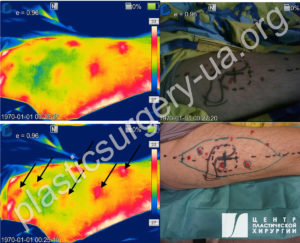

При выборе метода реконструкции обязательно следует брать во внимание онкологические процессы анамнезе, и особенно была или нет лучевая терапия в реципиентной зоне или области выкраивания лоскута. Решающее значение для выбора типа операции будет оценка состояния тканей и оценка кровообращения на локальном уровне. Мы считаем, что у пациентов, где предполагаются любые проблемы с сосудами, связанные с пожилым возрастом, травматическим повреждением или активным патологическим процессом, обязательным элементом предоперационной подготовки должна быть ангиографическая визуализация с МКТ[1], описанная нами в работах [40,41,42]. Она позволяет полностью избежать интраоперационніх «сюрпризов» и достоверно сократить время работы в операционной (Рис. 55,56).

Рис. 55. Предоперационная визуализация перфорантов на передней поверхности бедра перед свободной пересадкой ALT лоскута. На термограммах (слева) видны «горячие» точки выхода сосудов в кожу (маркированы стрелками). На цифровом фото(справа) разметка дизайна ALT лоскута на передней поверхности бедра, маркированы точки выхода перфорантов в кожу по данным аудиодоплера, четко совпадающие по локализации с данными термограммы.